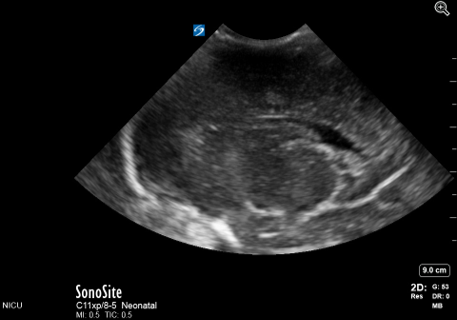

Neonatology Grade 1 IVH Pitfall 2 Image